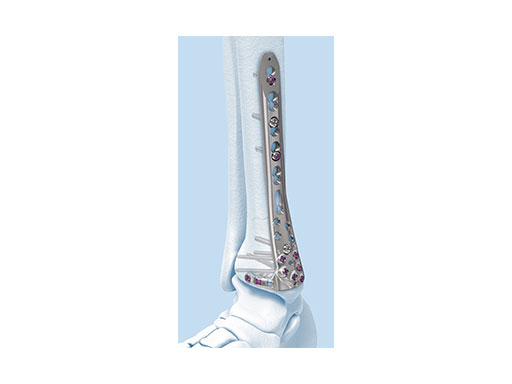

The Combi holes in the Variable Angle LCP plate shaft combine a dynamic compression unit hole with a variable angle locking screw hole. Due to the smaller sized and more numerous fixation options distally with 2.7 mm VA screws, the fixed-angle construct provides advantages for small metaphyseal segments where traditional screw fixation can be limited. The screw trajectories are optimized to support the distal articular surface. The multiple variable angle locking holes in the plate head accept 2.7 mm VA locking, 2.7 mm locking, 2.7 mm cortex, and 2.7 mm metaphyseal screws. The latter has a low profile screw head to avoid soft tissue irritations and can be used to pull the plate to the bone. Due to the numerous screw possibilities, it is important that the surgeon is familiar with which screws can be used in which plate holes. The system includes guide blocks for all plates (except T and L plates) for inserting screws in the plate head at nominal screw angles (Fig 1a-c). K-wire holes in the plate head and shaft tip accept K-wires up to 1.6 mm. They can be used to temporarily reduce articular fragments, and to confirm the location of the plate relative to the distal tibia and fibula.